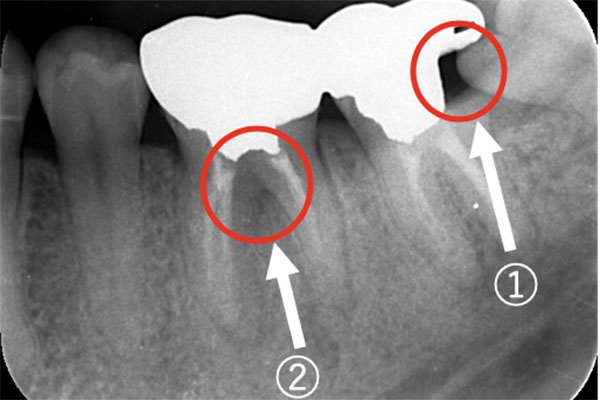

【担当医師所見】

①親知らず手前の歯はクラウン(白い不透過像)直下に大きな透過像(黒い部分)が見られこのような場合は抜歯になる確率が高いです。

②歯根分岐部(中央部)に及ぶ歯周炎ー根尖性歯周炎の原因はクラウン除去後にマイクロスコープ下にて破折線を確認したため抜歯となりました。